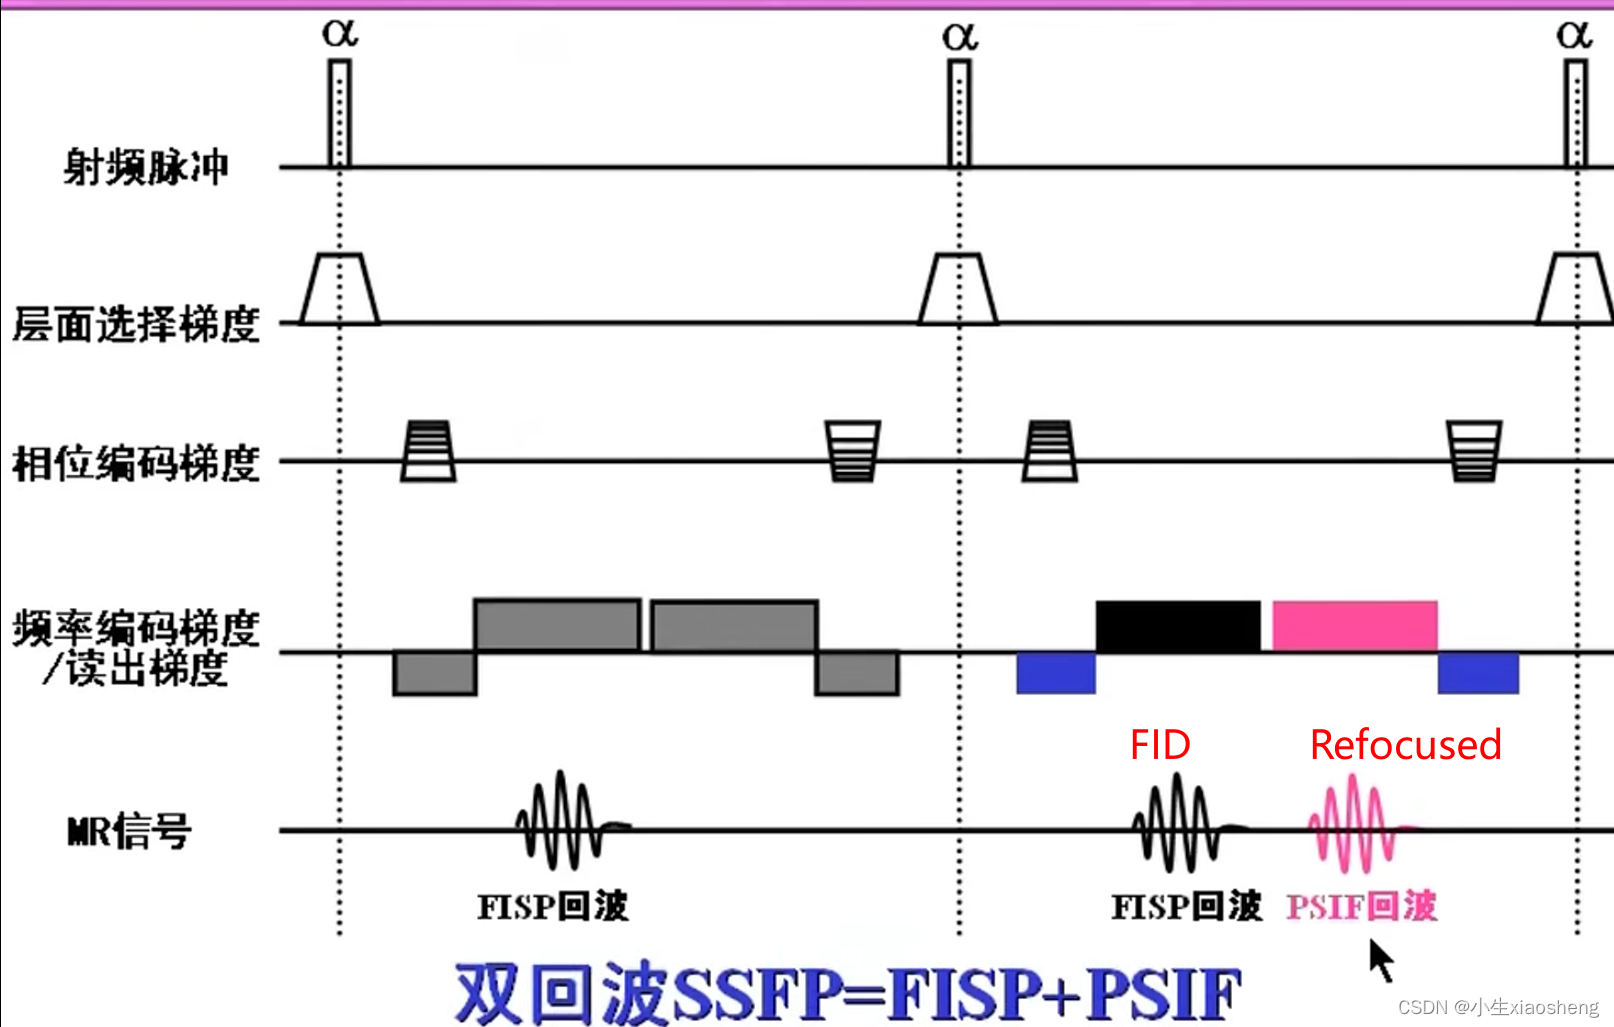

6.采集双回波的SSFP序列

它在每个TR(重复时间)周期内采集两个回波信号,通常称为“双激发”或“双回波”技术。在SSFP序列中,射频脉冲和梯度场被连续应用以产生稳态的进动信号。在双回波SSFP序列中,可以通过调整射频脉冲和梯度场的参数来在每个TR周期内激发并采集两个回波信号。

这两个回波信号可以通过不同的方式来获取和利用。一种常见的方法是使用两个不同的读出梯度场来分别采集两个回波,这两个回波可以具有不同的对比度和分辨率特性。通过这种方式,可以同时获取到关于组织结构的更多信息,提高图像的质量和诊断的准确性。目前也用的少